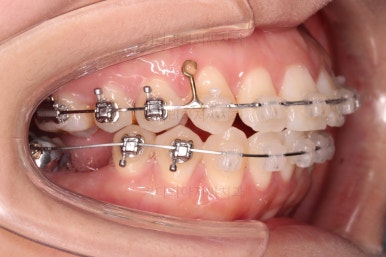

장치를 부착해서 가지런하게 하고요.

발치가 필요한 치아를 하나씩 뽑아나갑니다.

어금니 발치 공간이 어마어마하게 넓죠?

저 공간만큼 앞니가 들어가도록 하면 큰일납니다. 입이 너무 많이 들어가게 됩니다.

따라서 매우 신중한 테크닉으로 입매 조절을 잘 해야 합니다.

이번 부산사랑니교정 환자분이 선택하신 장치는 데이몬 클리어라고 하는 자가결찰 세라믹 장치인데요.

현존하는 세라믹 장치 중에 가장 심미적인 장치입니다.

철사를 잡아주는 뚜껑은 금속으로 되어있는 클리피씨나 엠파워 클리어에 비해 뚜껑까지도 세라믹으로 되어있기 때문이죠.

이제 미니스크류가 등장합니다.

상하좌우 발치 공간의 크기와 위치가 제각각이라서 당겨지는 양과 속도가 차이납니다.

그래서 미니스크류를 반드시 써줘야 합니다.